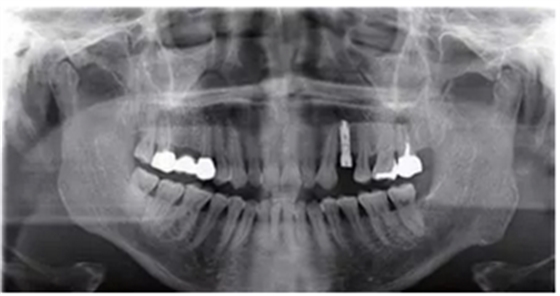

種植完成后可以通過拍攝曲面體層或是根尖片來確認(rèn)種植體的植入情況,并作為資料加以保存。

種植手術(shù)完成2周后進(jìn)行拆線??梢钥闯鲕浗M織愈合良好。

圖7 曲面體層片